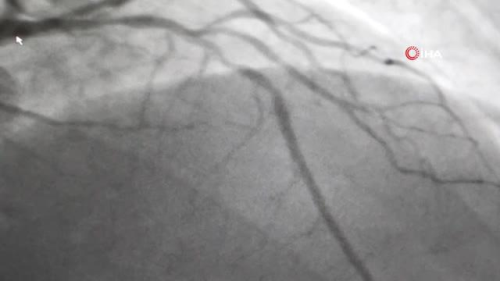

İSTANBUL - Kartal Koşuyolu Yüksek İhtisas Eğitim ve Araştırma Hastanesi Kardiyoloji Uzmanı Doç. Dr. Gültekin Günhan Demir, sağlıklı bir bayram geçirebilmek için tüketicilere uyarılarda bulundu. Demir, "Kolesterol ve kalp damar problemi olanlarda illa kırmızı et tüketmeleri gerekmiyor. Beyaz etin tercih edilmesi önerdiğimiz bir durum" dedi. Sağlıklı ve dengeli beslenmenin kalp sağlığı için çok önemli olduğu uzmanlar tarafından belirtiliyor. Özellikle Kurban Bayramı'nda şeker ve tatlı tüketiminin yanında kırmızı et tüketiminin de artması, kalp ve damar hastalığı ve şeker ve kolesterol hastalığı olan hastalarda ciddi sağlık problemlerine neden olabilmekte. Bu problemlerin önüne geçmek için Koşuyolu Yüksek İhtisas Eğitim ve Araştırma Hastanesi Kardiyoloji Uzmanı Doç. Dr. Gültekin Günhan Demir, hastalara bayramda dengeli beslenme konusunda uyarılarda bulundu. "Bayramda çok yoğun bir şeker ve tatlı tüketimi oluyor. Bundan da uzak durmak gerekiyor" Doç. Dr. Gültekin Günhan Demir, "Bayram sabahları vatandaşlarımız kahvaltıyı es geçiyor. Bu doğru bir tutum değil. Çünkü hem uzun süre kan şekeriniz düşük seyrediyor ve sonrasında uzamış açlığın etkisiyle ağır bir öğün tüketerek kan basıncımızı, kolesterolümüzü ve şekerimizi yükseltmiş oluyoruz. Kahvaltıda karbonhidrattan daha çok proteinlerin yer aldığı süt ürünleri ve yumurtanın yer aldığı bir kahvaltı yaparsak daha sağlıklı bir tercih olur. İlk gün kesilen etin ağır bir kokusu olabiliyor. Bazı insanlar rahatsız ettiği gerekçesiyle yoğun bir tuz kullanımı oluyor. Bu da kan basıncımızda dalgalanmalara yol açabilir. Kurban etine ekstradan tereyağı eklemeleri oluyor. Kurban etinin kendi yağı ve suyunda pişirilmesi daha uygun seçenek. Kavurma ve kızartmayı önermiyoruz daha çok ızgara haşlama ve fırınlama öneriyoruz. Etin porsiyonunu küçülterek yanına salata ve bulgur pilavı gibi eklemeler yaparak lifli içerikler sayesinde sindirimi kolaylaştırmak mümkün olabilir. Bayramda çok yoğun bir şeker ve tatlı tüketimi oluyor. Bundan da uzak durmak gerekiyor. Kolesterol ve kalp damar problemi olanlarda illa kırmızı et tüketmek gerekmiyor bayramlarda. Beyaz etin tercih edilmesi önerdiğimiz bir durum. Bayram ziyaretlerinde yürüyerek gitmeyi öneriyorum. Özellikle bunu kalp damar ve hipertansiyon problemleri olan hastalar için söylüyorum" dedi.